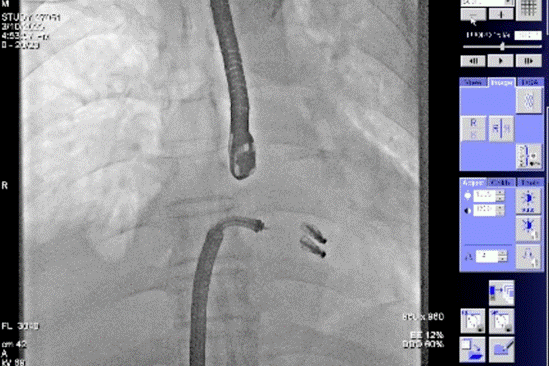

患者全麻成功后,经右股静脉建立路径,穿刺房间隔,瓣膜夹通过输送系统送入左心房,顺利到达病变二尖瓣区域。在经食道超声和DSA的辅助下,通过反复评估二尖瓣返流位置、抓捕位置、返流程度,最终在A2P2位置植入一枚DragonFly™夹子。手术操作时长48分钟,透视时间总计为5分钟,术后患者无不适感,整个手术流畅完美,患者返流程度降至微量。

患者全麻成功后,经右股静脉建立路径,穿刺房间隔,瓣膜夹通过输送系统送入左心房,顺利到达病变二尖瓣区域。在经食道超声和DSA的辅助下,通过反复评估二尖瓣返流位置、抓捕位置、返流程度,最终决定在A2P2位置植入俩枚DragonFly™夹子,显著改善了患者的返流情况。手术操作时长60分钟,透视时间总计为15分钟。术后患者无不适感,整个手术流畅完美,患者返流程度从重度降至轻度。